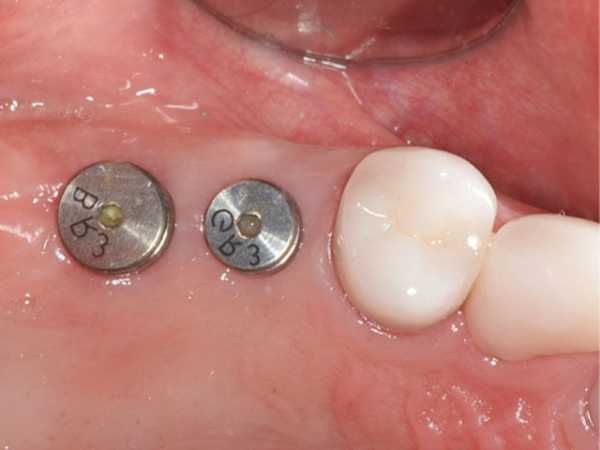

После установки устройства выполняется ушивание десны. Рану зашивают хирургическими нитями узлового типа. Швы снимают через неделю после операции. Имплант не ставят сразу же после удаления естественного зуба, так как это провоцирует дополнительное травмирование мягких тканей. После зашивания происходит установка формирователя десны, который придает мягким тканям естественный внешний вид. Его монтаж происходит после сращения структур челюсти с металлическим штифтом.

На фото изображены 2 импланта с формирователями десны

Адаптационный период после установки имплантов на верхнюю челюсть длится долго (более 3 месяцев). Это связано с тем, что верхняя челюсть имеет менее плотную структуру, чем нижняя. В последнем случае адаптационный период составляет не более 1 месяца. Перед установкой заглушки стоматолог еще раз оценивает качество проведенных ранее работ при помощи рентгенографии. Через 2 недели после процедуры ставят абатмент.